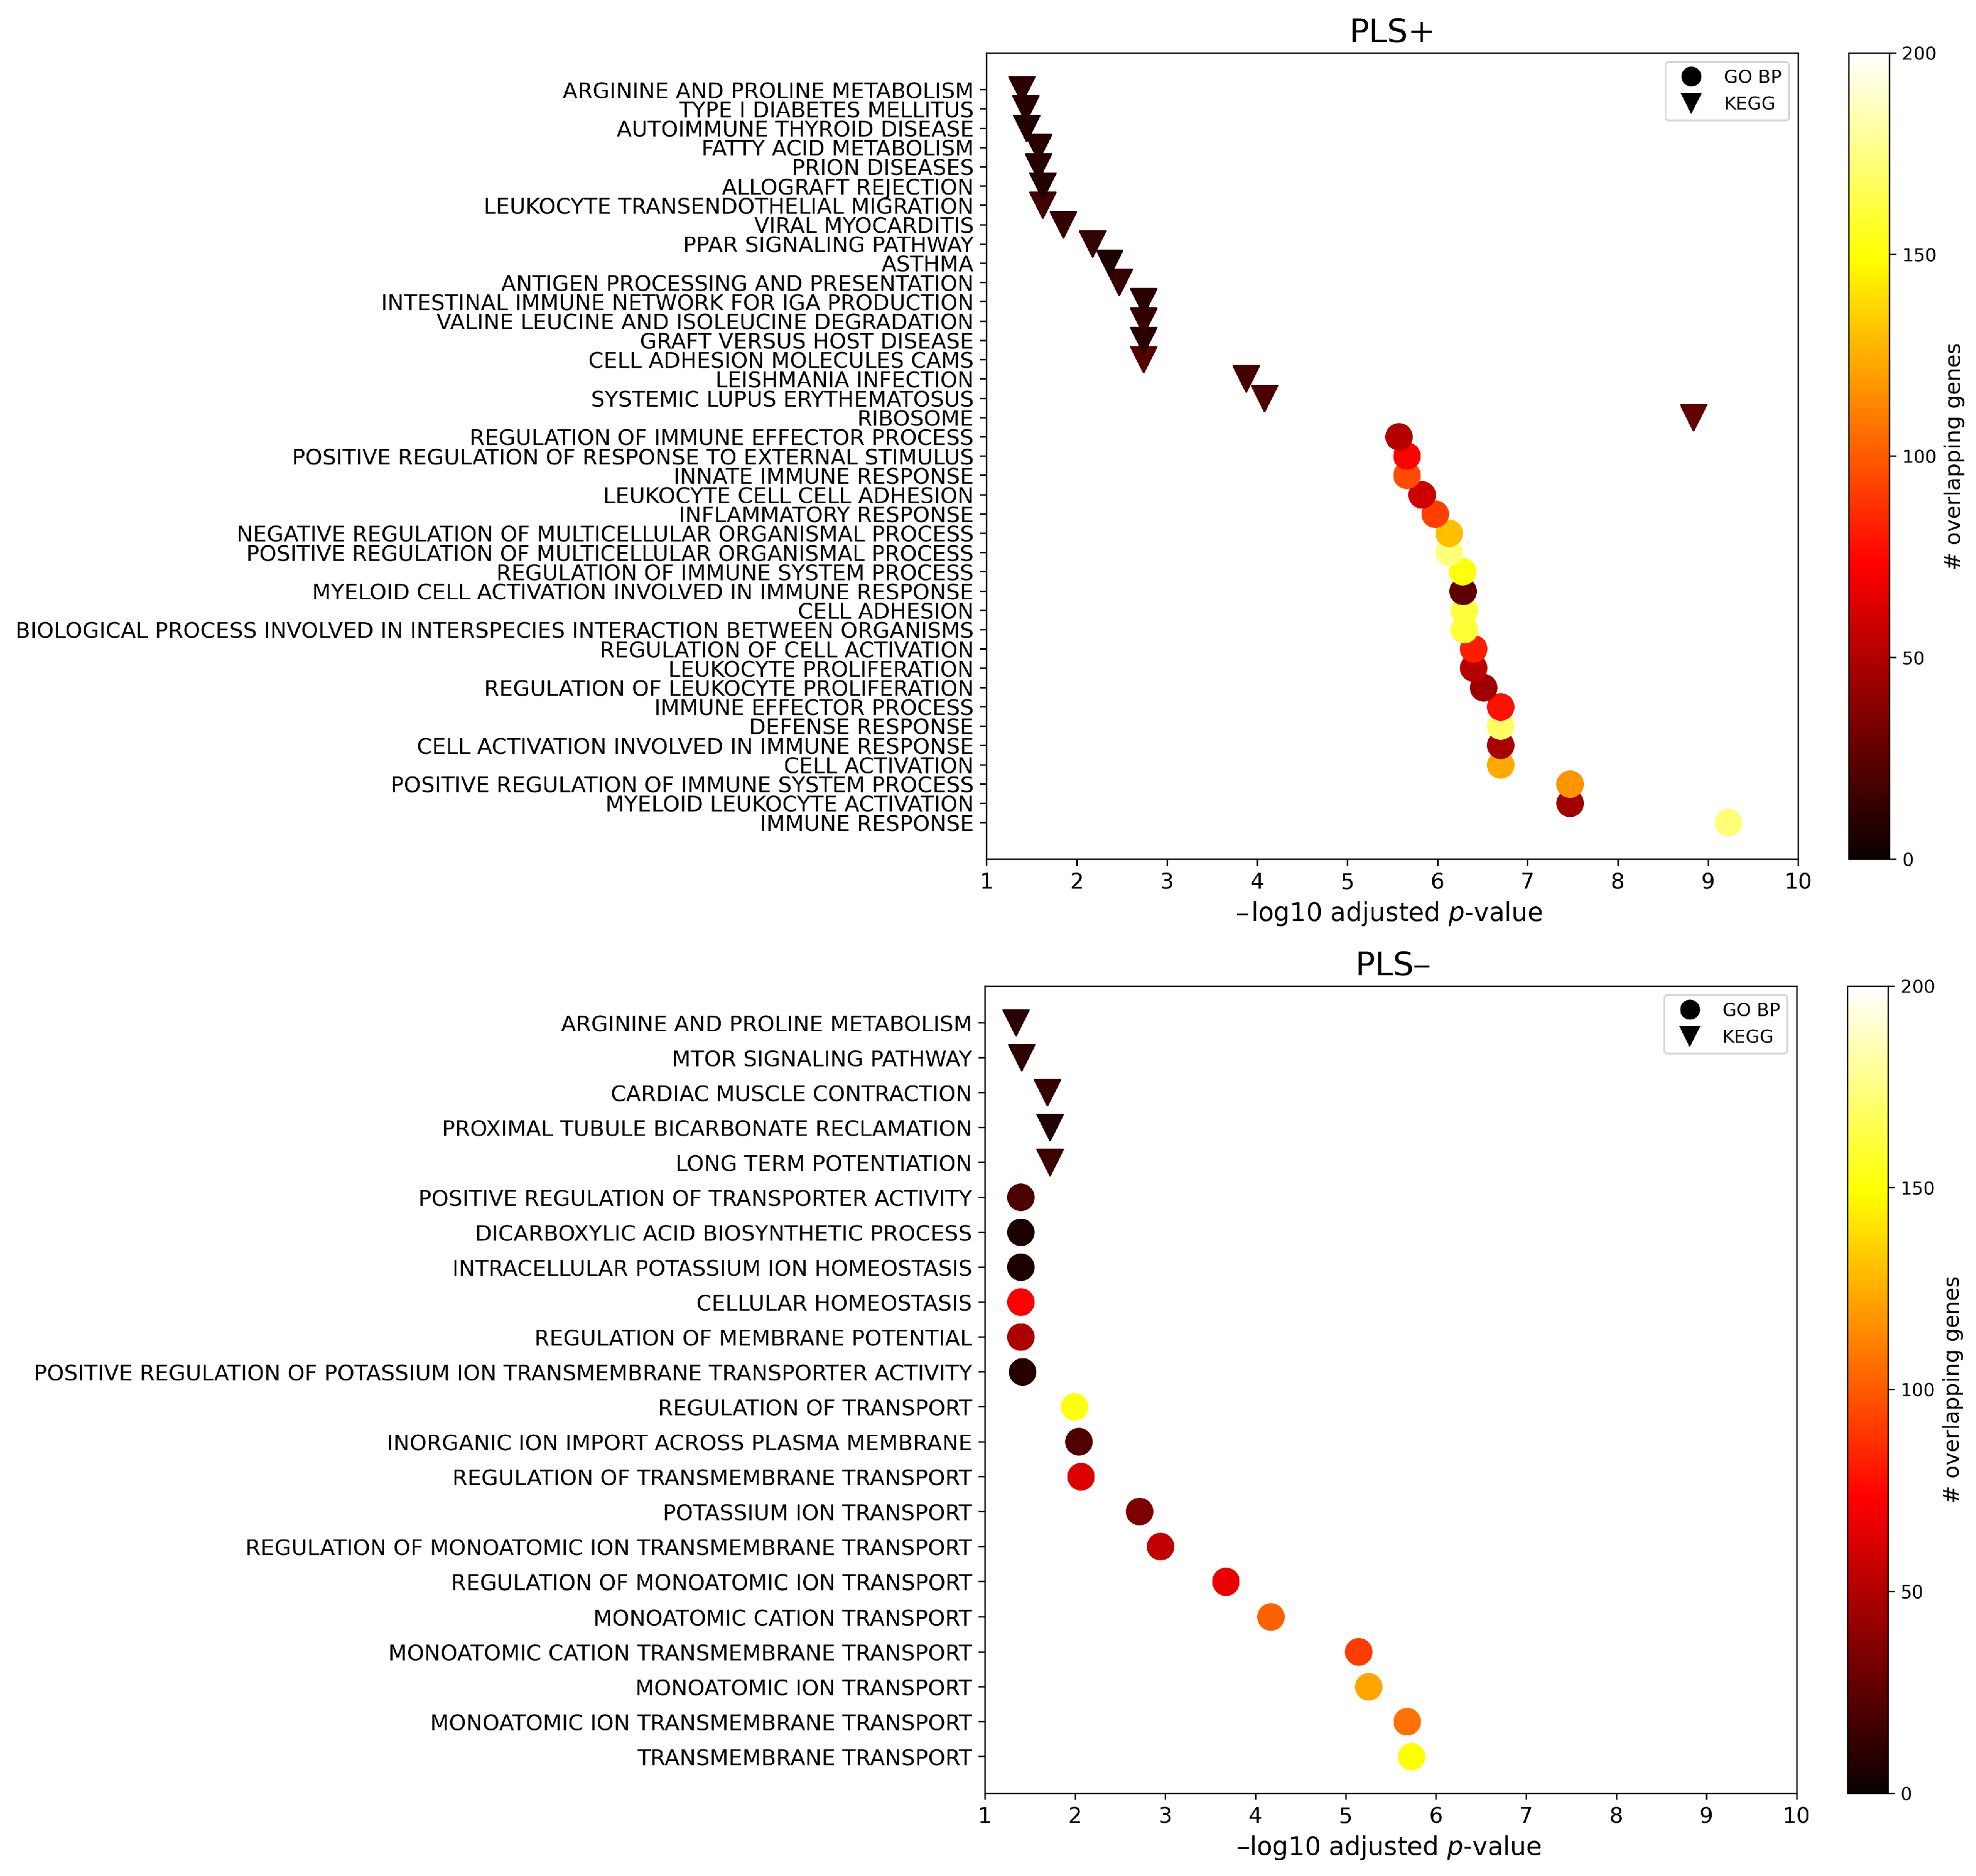

2.3. Enrichment Analysis